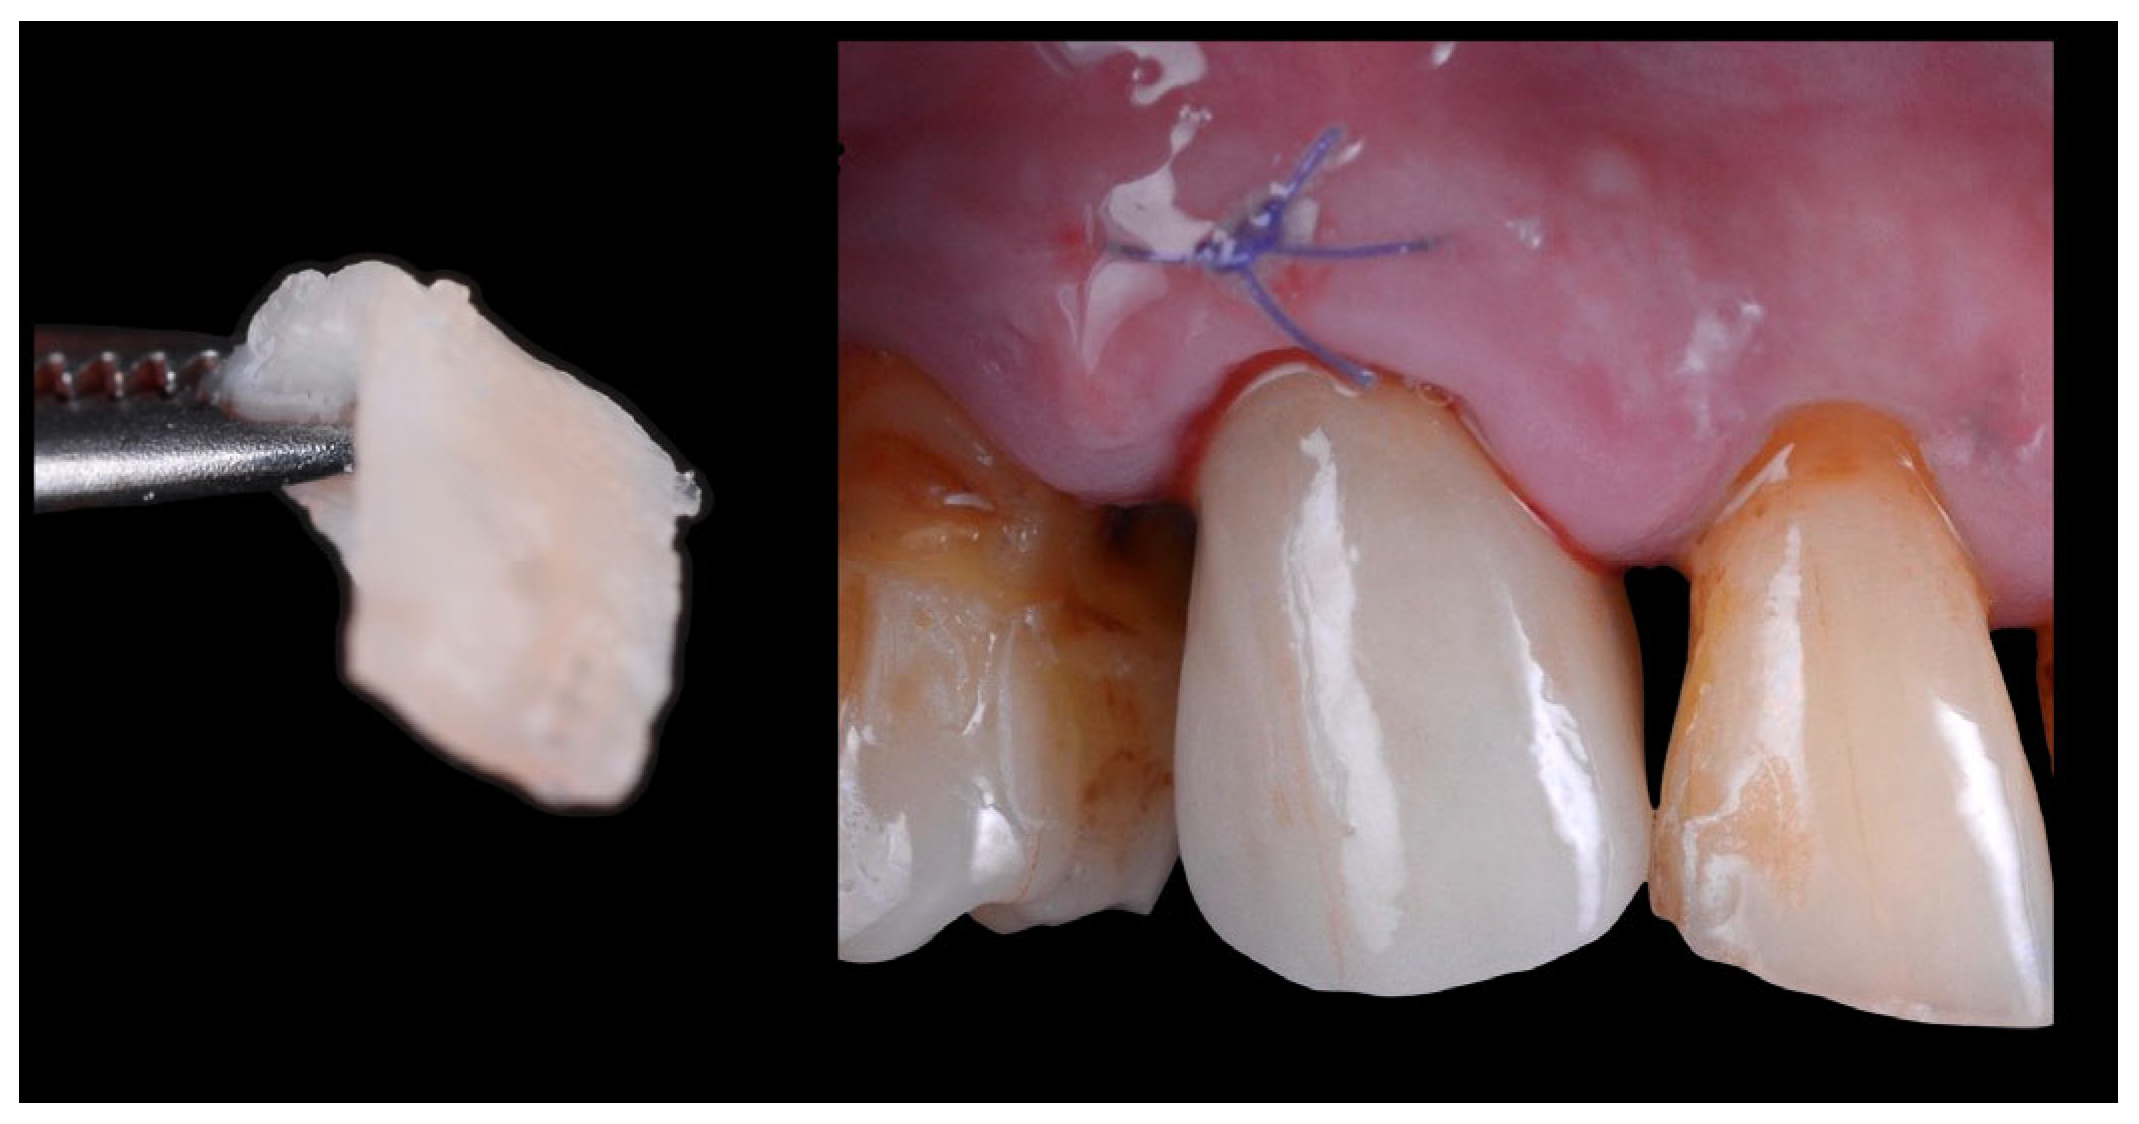

2.4. Crown Delivery

2.5. Definitive Overlay Adhesion